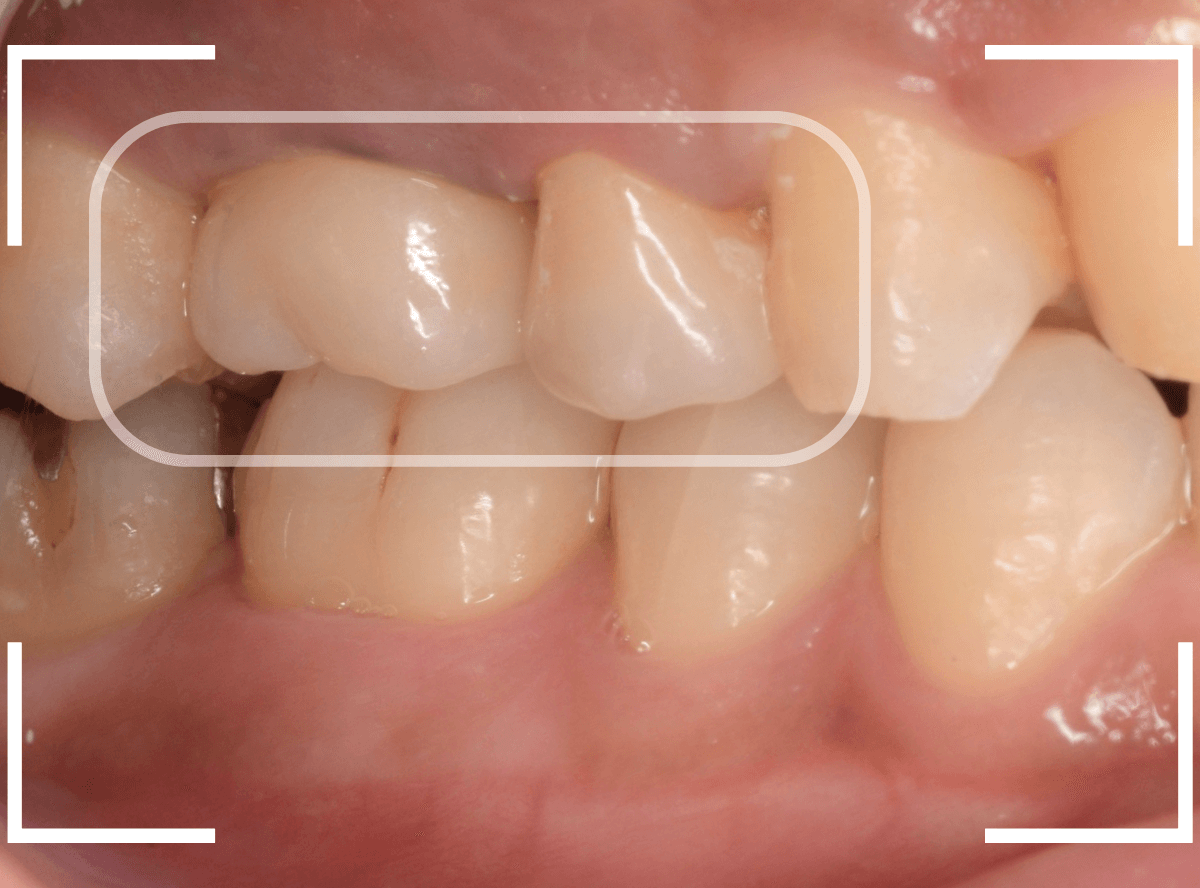

以前に治療した上のさし歯を綺麗にやり直したいというご相談の患者さんです。

保険診療で行うさし歯「レジン前装冠」が入っています。

「レジン前装冠」は裏から撮影した写真を見ていただければわかるように、銀歯の上にレジン(プラスチック)を盛ったさし歯で、実質的には銀歯です。

銀歯の上にプラスチックを盛るために、歯をかなり大きく削る必要があったり、短期間で劣化・変色する(この方の差し歯も劣化してのっぺりした黄土色になっています)、金属の色素が歯肉に溶け出して歯肉が黒くなる(メタル・タトゥー)などのデメリットがあります。

さて、この方の歯の形を確認すると、左右でかなり歯の長さに差があります。